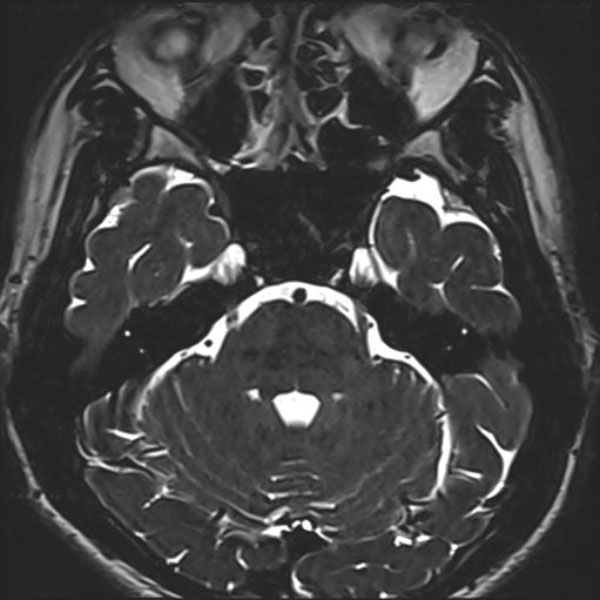

手術前

(MR1)